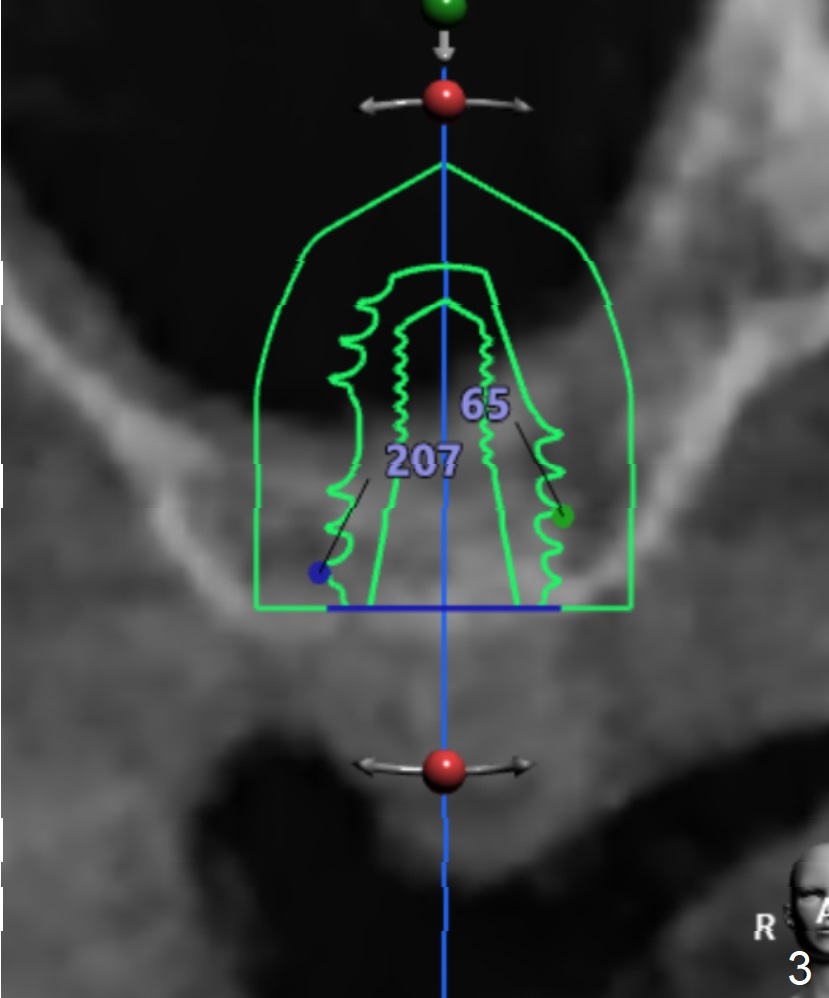

The implant size I tried was 5.0 X 7.3mm and it seems like bone density is quite low.

Undersized drilling suggested (at least 2 size smaller to get more fixation). And on the facial view there's 4mm of remaining bone but on the buccolingual view, there's less than 3mm. It would be much better if you could plan to do a lateral sinus elevation in this case.  Jennifer